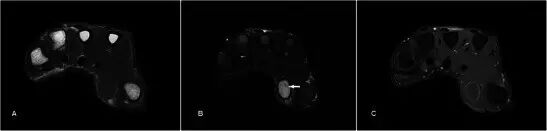

软骨肉瘤是成人中最常见的原发性骨恶性肿瘤,并且可以作为良性软骨瘤损伤(例如软骨瘤)的恶性变性发生。 平片显示典型的“环 - 弧”矩阵,其具有内皮层扇形和皮层变薄,但是在更高级别的亚型中,经常存在骨折破坏和不规则边缘[50](图19a)。 MR通常用于局部分期(图19b-d)。 对远端指骨的病变的鉴别诊断是血管球瘤,但是显示主要可扩展的骨病变的平片显示有效地排除了它。

图19.低级软骨肉瘤在一个47岁的女性,呈现一个缓慢扩大的企业肿胀左侧小指的远指骨几个月与指甲畸形。 (a)平片显示在小指的远指节中的可扩张的裂解性骨病变,具有标记的内皮层破裂和随着背侧皮层的破坏而变薄。 环 - 弧密度暗示着软骨形成基质(箭头)。 (b)T1w序列显示在中指的小指远端指节中的可扩展的骨病变,软组织成分破坏并穿透背皮质以涉及皮肤和指甲。 (c)在具有低信号区域(箭头)的T2w-FS序列上,病变是非常高的信号,典型的软骨形成基质。 (d)后对比度有异质增强